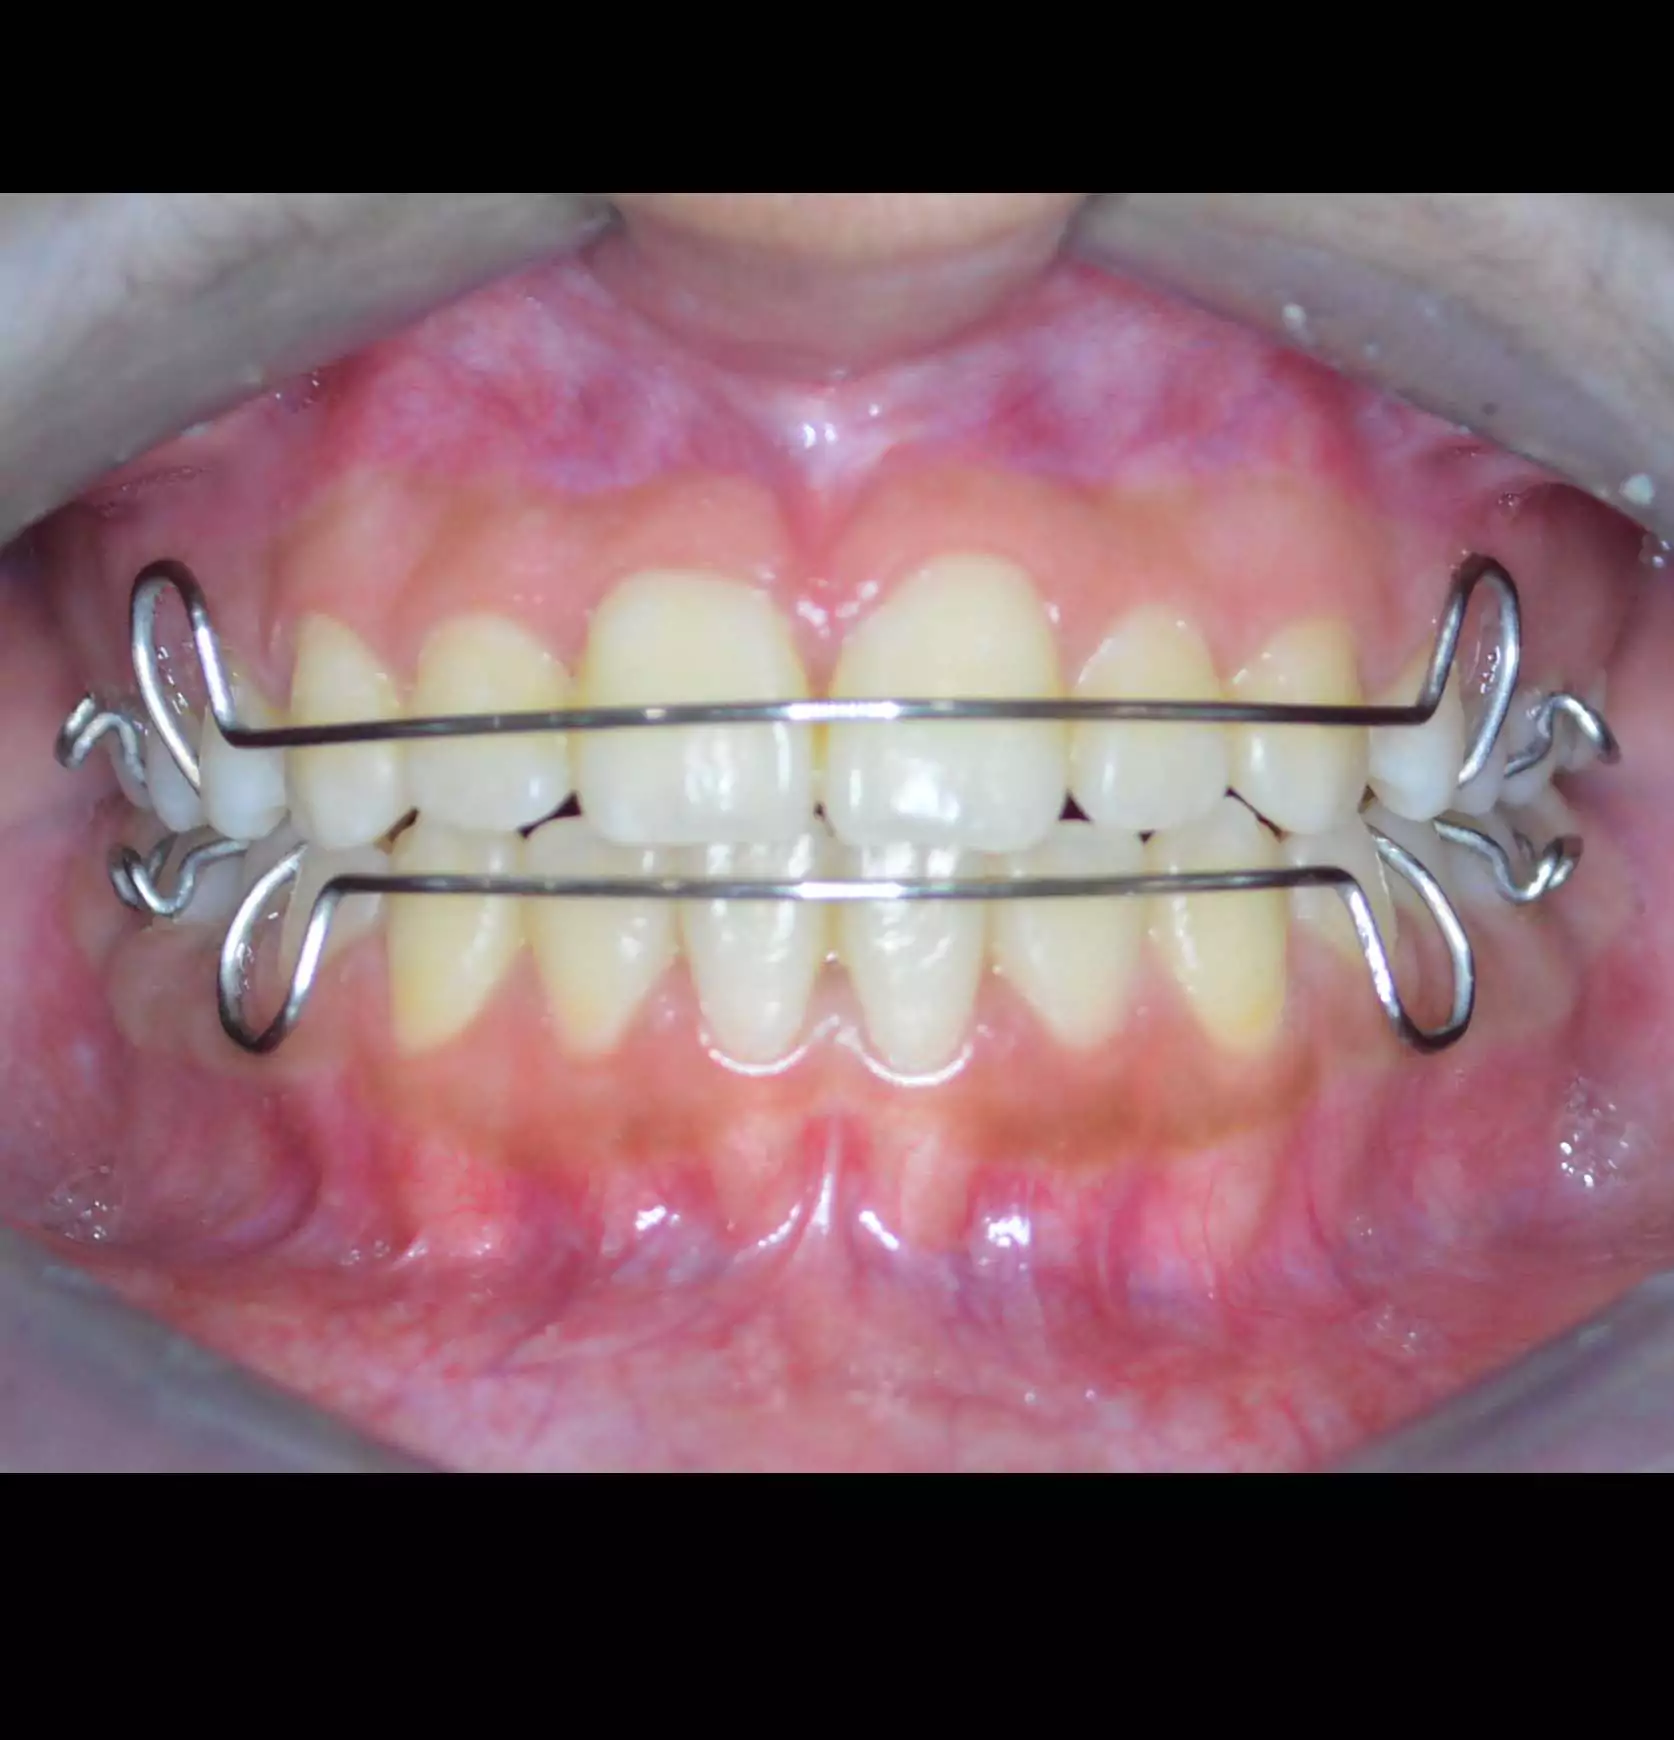

Anterior Crossbite Correction

Without Extraction Of Teeth

A young newly married female had crossbite in front teeth and when she smiled she felt her teeth appeared crooked. Being newly married she also had concerns regarding wearing braces. Assessing the situation, we advised ceramic braces and treated the condition without extracting or removing any teeth.

Pre Treatment

The treatment was completed successfully after a period of 18 months. Our patient is now embarked on her newly married life with more confidence.